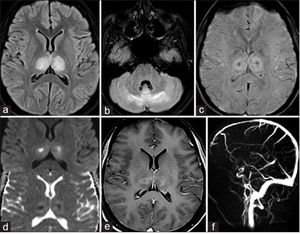

Dengue Doughnut

Dengue doughnut: A diagnostic magnetic resonance imaging finding in dengue encephalitis.